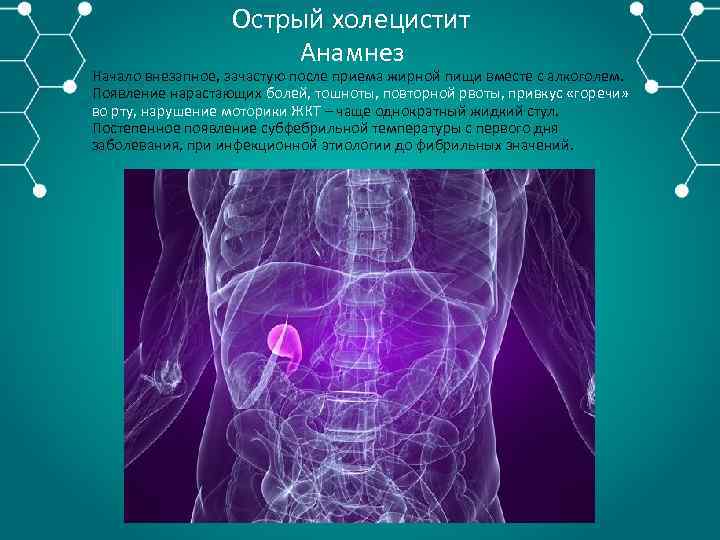

Острый холецистит Анамнез Начало внезапное, зачастую после приема жирной пищи вместе с алкоголем. Появление нарастающих болей, тошноты, повторной рвоты, привкус «горечи» во рту, нарушение моторики ЖКТ – чаще однократный жидкий стул. Постепенное появление субфебрильной температуры с первого дня заболевания, при инфекционной этиологии до фибрильных значений.